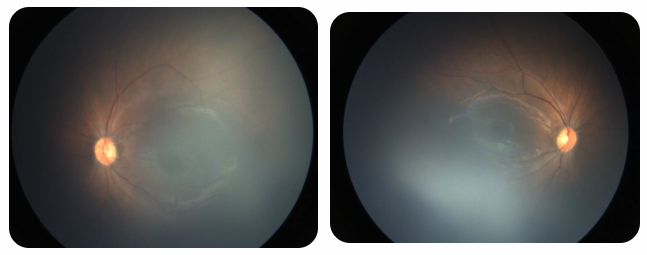

廈門眼科中心黎曉新名醫(yī)工作室曾接診一名31周出生的早產(chǎn)兒,出生體重僅1300克。由于家長(zhǎng)缺乏篩查意識(shí),直到孩子5個(gè)月大時(shí)眼睛仍不會(huì)追光,才前來就診。檢查發(fā)現(xiàn),患兒ROP已進(jìn)展至4B期,因纖維血管增殖牽拉導(dǎo)致視網(wǎng)膜脫離,錯(cuò)過了最佳治療窗口。盡管黎曉新教授團(tuán)隊(duì)成功實(shí)施了玻璃體切割手術(shù),孩子的視力仍存在不可逆損傷。此后,孩子開啟了長(zhǎng)期隨診復(fù)查、治療的“護(hù)眼征程”,目前其右眼矯正視力為0.6,左眼為0.8。

近期術(shù)前檢查:

早產(chǎn)兒視網(wǎng)膜病變

術(shù)后復(fù)查:

相比之下,另一位早產(chǎn)寶寶在出生5周后,生命體征穩(wěn)定之時(shí),便在產(chǎn)科醫(yī)生的建議下轉(zhuǎn)診至廈門眼科中心。經(jīng)篩查確診為Ⅲ期ROP,黎曉新教授團(tuán)隊(duì)及時(shí)為其進(jìn)行了激光治療。半年后復(fù)查顯示,寶寶的視網(wǎng)膜血管發(fā)育正常,視力發(fā)育與足月兒童無異。